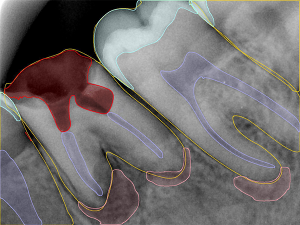

- Disease Detection

ldentify Key Pathologies for Clear VisualCommunication

- Tooth Structure Analysis

Automatic anatomical segmentation to support clinical decision-making